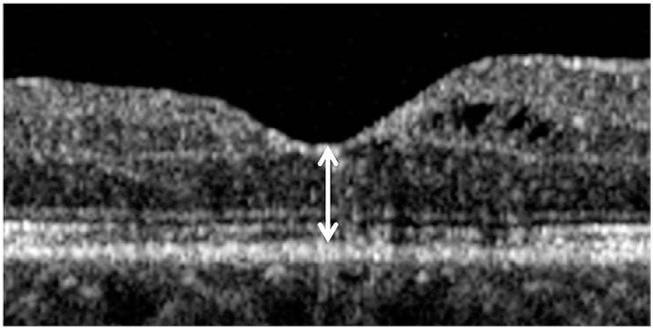

To evaluate patients' self-recognition of reduced visual acuity due to recurring macular edema in retinal vein occlusion.

A retrospective review of medical records of patients who were diagnosed with recurring macular edema secondary to retinal vein occlusion was performed. The proportion of patients who recognized reduced visual acuity due to the recurrence of macular edema and who visited the hospital before the scheduled follow-up date was determined. Parameters including age, sex, diagnosis, visual acuity before recurrence of macular edema, and extent of visual acuity reduction due to recurrence of macular edema were compared in patients who recognized a reduction in visual acuity and those who did not. The proportion of patients who visited the hospital promptly was also determined.

Forty eyes of 40 patients were included in the analysis. Sixteen and 24 patients were diagnosed with central retinal vein occlusion and branch retinal vein occlusion, respectively. Twenty-one patients (52.5%) recognized reduced visual acuity due to recurring macular edema. These patients were younger (59.2 ± 7.6 vs. 64.8 ± 9.4 years, p = 0.046), had better visual acuity before recurrence of macular edema (0.52 ± 0.48 vs. 1.02 ± 0.46, p = 0.002), and exhibited a greater reduction in visual acuity after recurrence of macular edema (0.34 ± 0.24 vs. 0.14 ± 0.13, p = 0.003). Only four patients visited the hospital before the scheduled follow-up date, and all of these patients lived relatively close to the hospital.

For prompt treatment of recurring macular edema, more intensive education about the self-estimation of visual acuity is necessary, particularly for elderly patients who have relatively poor visual acuity. In addition, a simple and easy way to identify the recurrence of macular edema at the local clinic should be established for patients who live relatively far from the hospital.